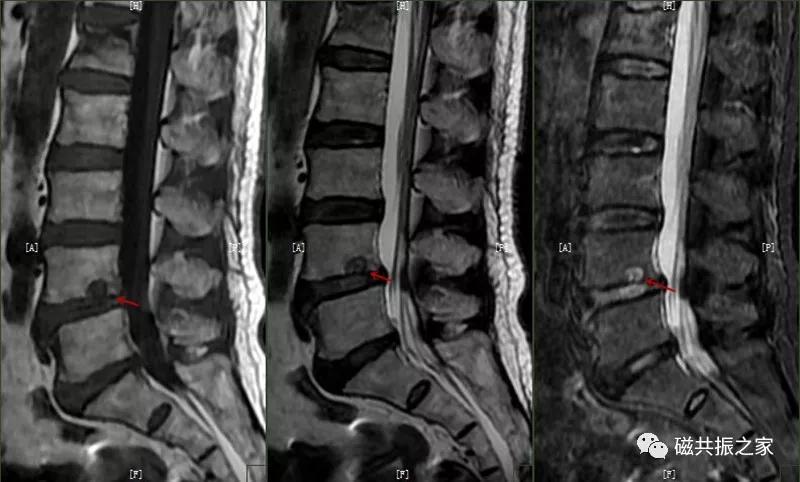

12.休门病/许莫尔结节/椎体边缘骨

休门病(Scheuermann,sdisease),主要由椎板骨软骨炎引起骨生长障碍,常见于青少年胸腰椎脊柱病变。

主要表现:椎体发育异常,椎体楔形改变,高度变低,前后径正常,常形成脊柱后凸畸形。

在矢状面上T1WI和T2WI显示各椎体楔形变,椎体高度减小,椎间隙变窄。椎体后1/3区呈多发性小骨质凹陷的Schmorl结节改变,髓核组织突入其中,边缘清楚,常呈上下对称分布,青少年病变周围可见长T1长T2信号,提示骨小梁水肿。

许莫尔结节(Schmorl,snodes),是休门病的一个病例征象。1930年Schmorl对照检查8000例尸检和X线发现椎体生长板发育不完善,或后天外伤致椎间盘突入椎体骨松质内,形成椎体压迹,是休门病的主要征象之一。除休门病外,其他的原因引起的生长板破坏,也可能产生Schmorl结节样改变。

矢状面显示椎体上或下椎间盘面异常信号,常呈长T,长T2信号,见髓核信号突入椎体内,常伴椎间隙变窄,常见于L3~S1椎体。

椎体边缘骨,类似于Schmorl改变,一类是椎体生长板和椎体二次骨化中心软骨发育异常,致其不能完全愈合,造成的椎间盘疝入其间,形成边缘体的椎体边缘骨。

另一类是椎体后缘骨内软骨结节,椎间盘疝入骨内,形成椎体后缘的Schmorl结节样改变,椎体终板及髓核等突入其中,椎体骨质增生,常见于L4、L5椎体下缘。